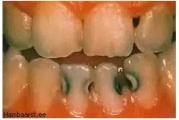

Fluoroos

Fluoroosi